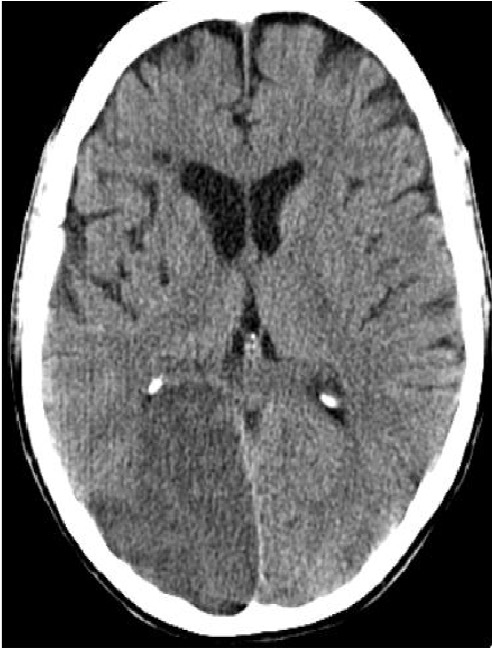

CT head without contrast is generally ordered to eliminate the possibility of an intracranial hemorrhage. You won’t see the signs of stroke until much later. However, you can see a hyperdense MCA sign sometimes.